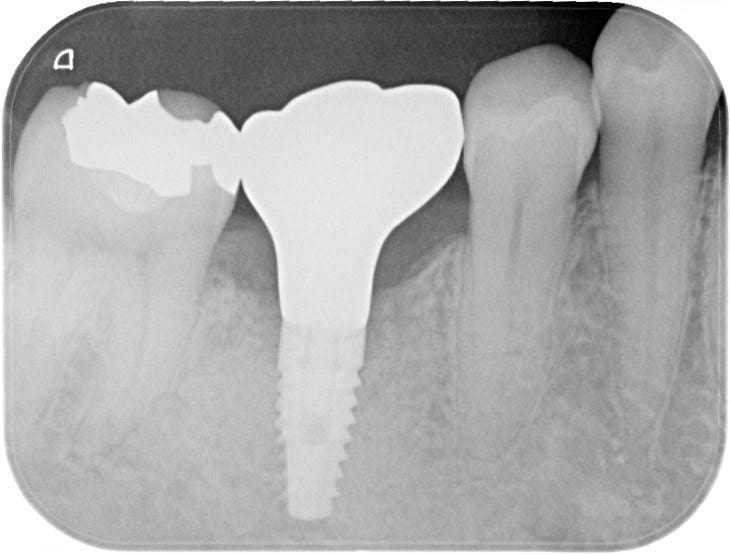

前医でインプラントの埋入角度が悪く、インプラント周囲炎になってしまった患者様の症例です。

インプラントが虫歯になることはありませんが、インプラント周囲炎というインプラントの歯周病にはなります。

インプラント周囲炎の主な原因は汚れ(菌)と力です。このように斜めに埋入されているインプラントは、真っ直ぐ埋入されているものに比べて汚れも溜まりやすく、噛む力も斜めにかかってしまうため、インプラント周囲炎になるリスクが大幅に高くなります。

この患者様は内側の骨が大幅に溶けてしまっていたので、前のインプラントを撤去して、骨を再生させると同時にインプラントを正しい位置と角度で埋入し直しました。溶けてしまっていた骨が治っていることもレントゲンでご確認いただけるかと思います。

インプラントは「どこの位置にどのような角度で入れるか」によって、一生使い続けられるかどうかの期待値が大きく異なります。値段だけを基準にクリニックを決めるのではなく、信用できる歯医医師と治療を進めることをお勧めします。